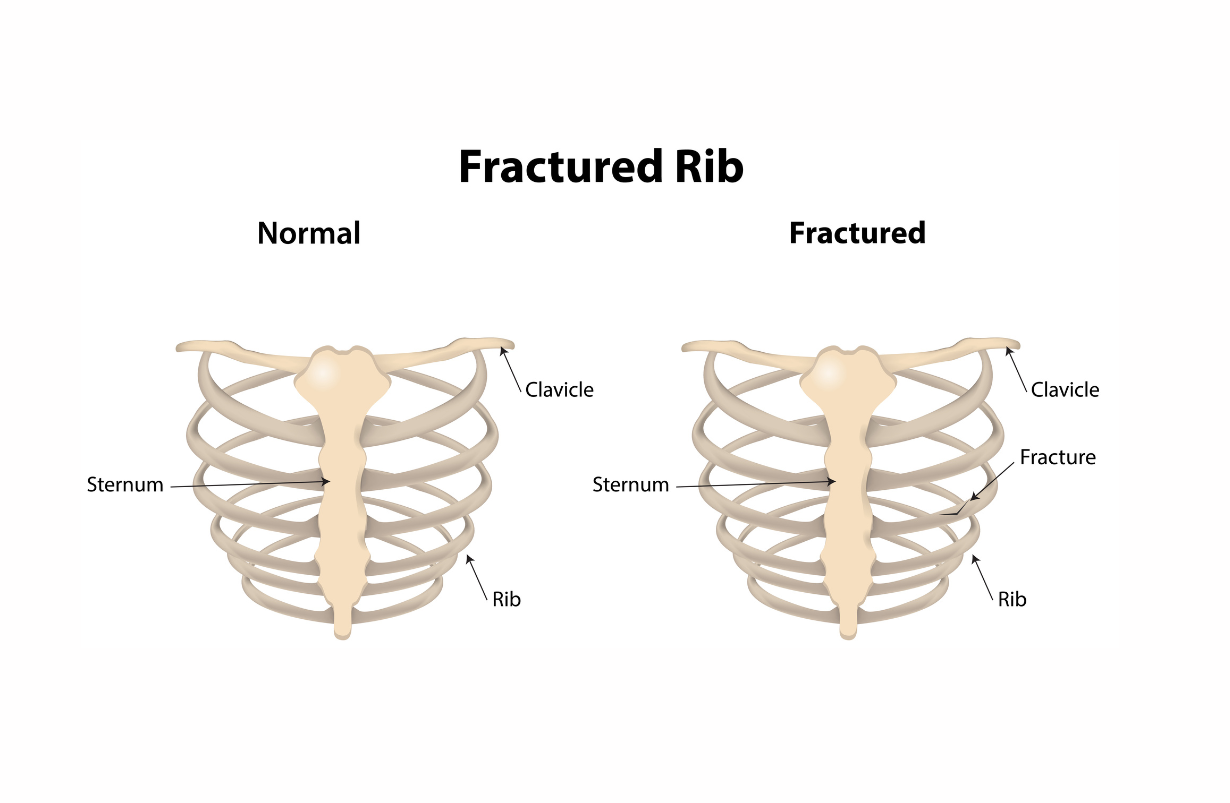

Rib Fracture

Ribs can fracture from falls, and in osteoporosis, from coughing or sneezing. Generally pain is severe, worsened by breathing, talking and (yes) laughter. X-rays are the definitive means of diagnosis, and often it takes 10 days to two weeks after the actual fracture for it to show up on X-ray films, because demineralization must take place. Very severe fractures, where the fragments of bone are at different angles, and there is danger to the internal organs because of their sharp edges will show up at once, Contraindications: Just about every yoga pose can be painful in the presence of a fractured rib. Twists, forward bends, back bends and even inversions can be tried, very cautiously. Treatment for all but these serious fractures is conservative: If it hurts, don't do it. Occasionally binding the chest is used to reduce pain. Severe fractures might require surgery. The pain gradually subsides and is generally gone in 6-8 weeks.